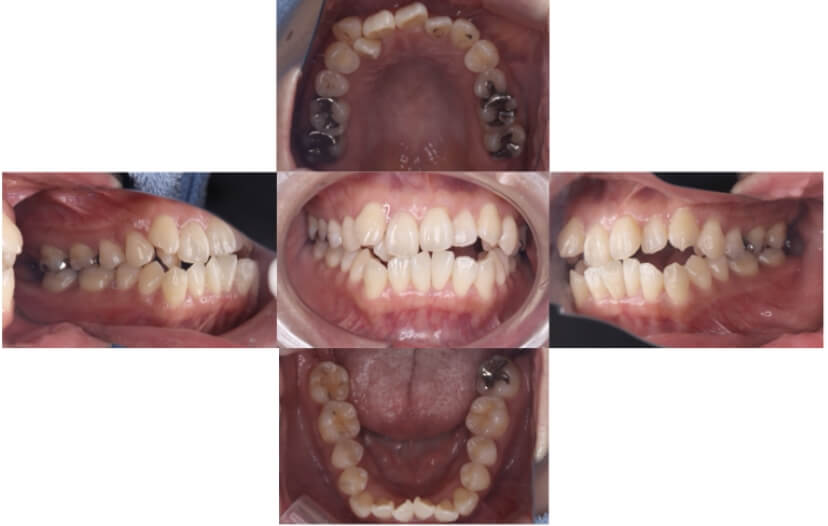

症例2

上下顎前突、叢生

抜歯

ブラケット矯正

上下顎前突、叢生(上下出っ歯、上下の前歯のガタガタ)のケースです。

装置はラビアル(上下表側)で、上下顎の小臼歯を4本抜歯を行っています。抜歯したスペースを使って、上下の前歯の後方移動と叢生(ガタガタ)の改善を行っています。

主訴 前歯のガタガタと口元がでているのが気になる。

年齢・性別 30歳 女性

お住まいの地域 東京都大田区

治療方針 抜歯スペースを利用して上前歯の叢生(ガタガタ)と口元突出の改善

抜歯部位 上下顎左右第一小臼歯

使用装置 ラビアル(上下表側)、顎間ゴム

治療期間 1年11か月

治療回数 13回

リテーナー クリアリテーナー

BEFORE

AFTER